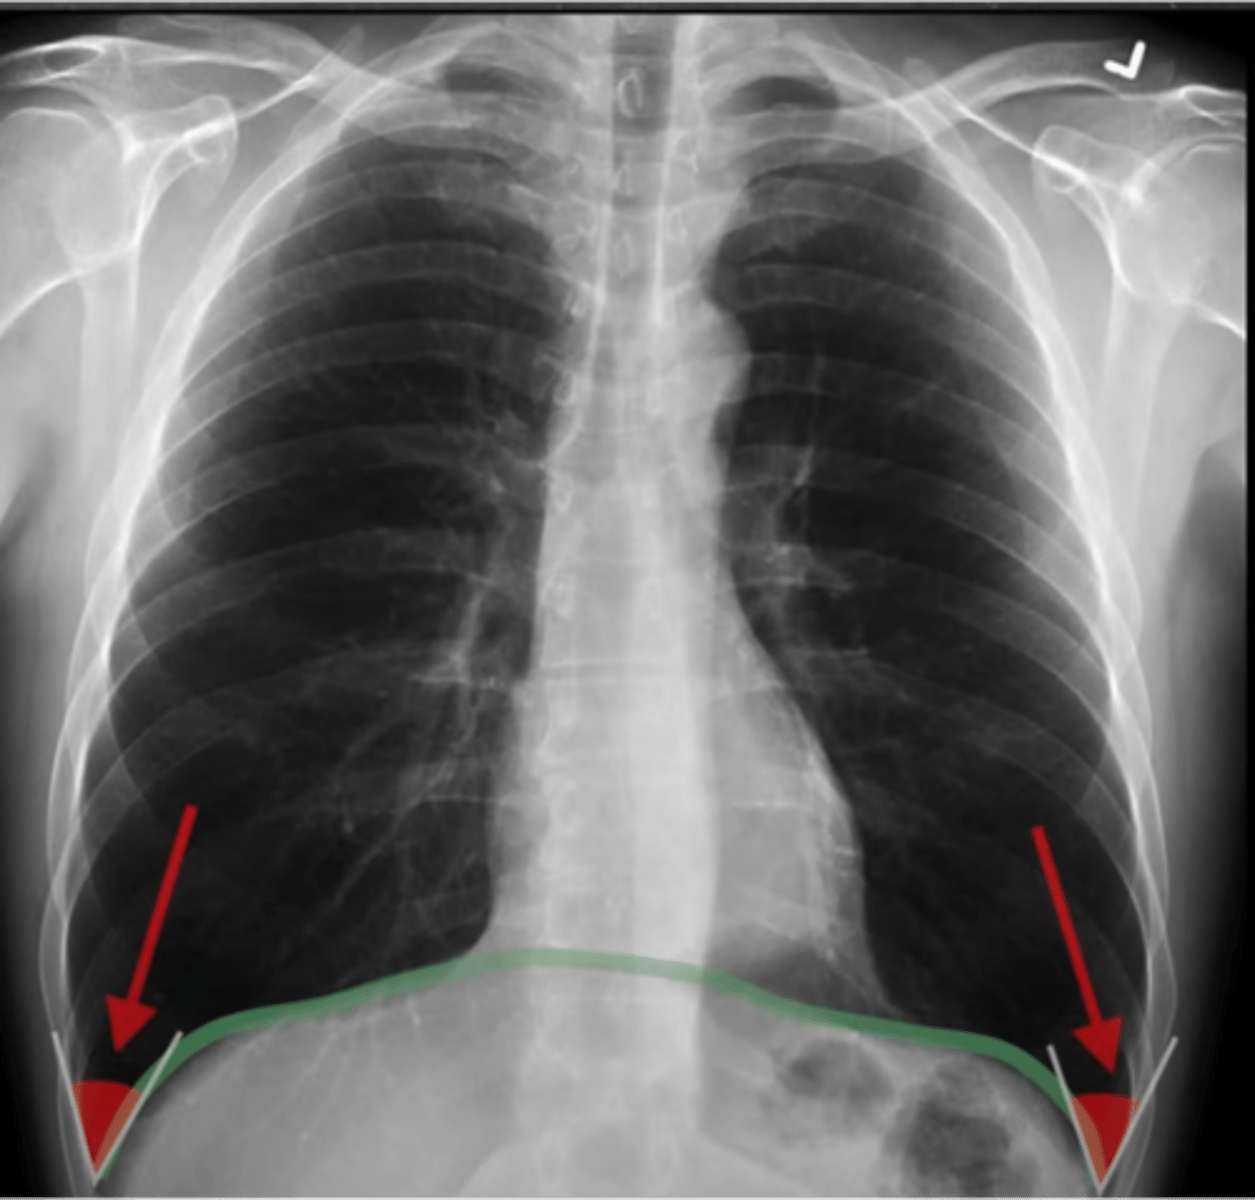

-sharp costphrenic angles on both sides

D: diaphragm

effusion

what can blunting of the costophrenic angles indicate

-blunts costophrenic angles

-haze over entire hemithorax (densest at base)

Pleural effusion on an XR